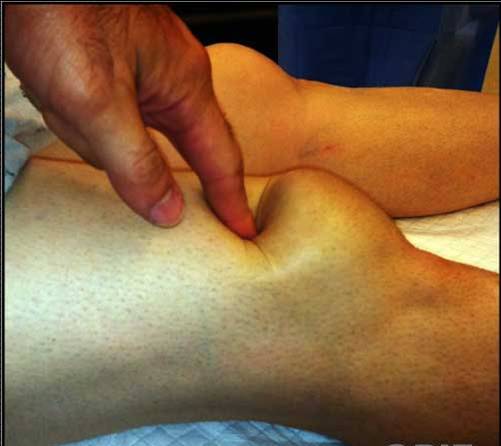

Pga hæmatom og hævelse kan senedefekten være svær at se, men er ofte tydelig at palpere.